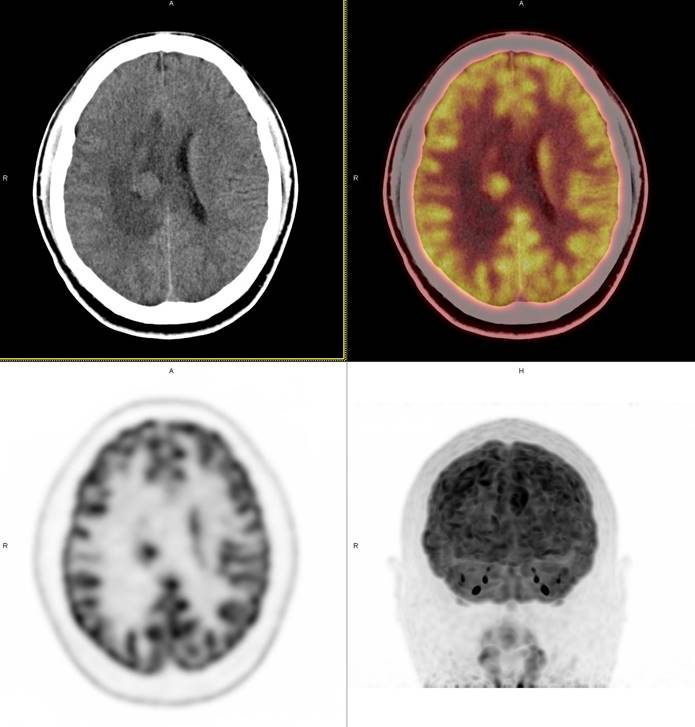

PET/CT影像圖

圖1

PET/CT檢查

影像診斷: 右側(cè)側(cè)腦室旁腦實質(zhì)內(nèi)結節(jié),代謝異常增高(SUVmax 12.13),伴瘤周水腫。

病理診斷:腦膜瘤二級

PET/CT鑒別診斷

正電子發(fā)射計算機斷層(positron emission tomography,PET)是一種分子成像技術,PET 應用 18F-FDG等顯像劑可顯示人體內(nèi)細胞、分子或者基因水平的生物學、病理學過程,進一步實現(xiàn)疾病早期定量與定性診斷。PET/CT使形態(tài)影像學與功能影像學得到了良好的結合,更有利于對腦膜瘤進行全面的評價。既往研究發(fā)現(xiàn),18F-DG PET/CT對診斷WHOⅠ、Ⅱ級腦膜瘤具有較高的敏感度,F(xiàn)DG攝取可用于評估腦膜瘤的腫瘤增殖情況,以此達到鑒別腦膜瘤的良、惡性的目的。有學者統(tǒng)計,WHOⅡ、Ⅲ級與 WHOⅠ級的平均標準化攝取值(standardized uptake value,SUV)分別為 2.51 (1.36,3.66)和 0.42 (0.12,0.73),WHOⅡ、Ⅲ級腫瘤與正常組織比率(T/N比率)存在差異,WHOⅡ級腦膜瘤的 SUVmax和最大T/N比率顯著高于 WHOⅠ級腦膜瘤。SUV和T/N比率對高級別腦膜瘤的診斷有較高的特異度。

此例,PET/CT全身檢查不僅排除了轉(zhuǎn)移瘤的可能性,增高的SUV值無創(chuàng)地鑒別腦膜瘤的良惡性,充分體檢PET/CT大視野、形態(tài)與功能影像結合的優(yōu)勢。